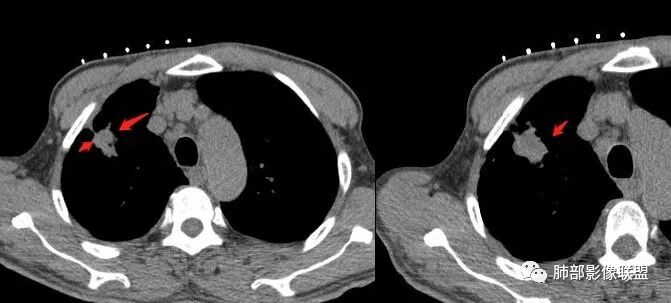

右肺上叶尖段病灶,边缘长、软毛刺,U型征,局部胸膜增厚牵拉,卫星灶。纵隔4R淋巴结增大。

深分叶、边缘膨隆、胸膜凹陷征及附近多发结节,胸膜不干净,纵隔多发淋巴结

但是呢,我觉得这个病灶,它确实有一些恶性的特点,边缘膨隆,深分叶,有深短毛刺。

感觉胸膜上有很多结节,层面不够,还有一点胸水。

南边:纵隔淋巴结有融合的迹象,边界不清,右侧内乳动脉增粗了很多;怀疑纵隔淋巴结用血很大。有结核的话并不代表不能得癌肿;一般情况下结核附近的病灶呈条索树芽状;综上所述恶性不能完全排除。